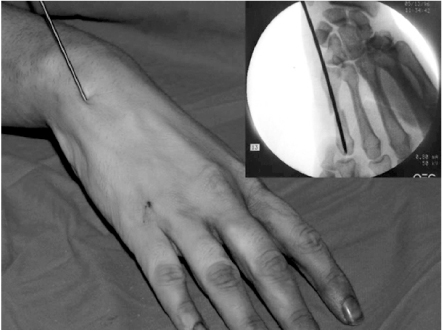

The surgery was performed under general or regional anesthesia with image intensification, preferably with a tourniquet on the upper arm. Under the fluoroscopy, closed reduction of the metacarpal fracture was achieved by manipulation, and 1.6 mm K-wire was inserted from metacarpal head with MP joint flexion for easy access to the medullary canal (Fig. 1). When the wire tip passed fracture site and reach to metacarpal base, wrist was bent maximum and further penetration was performed to proximal area (Fig. 2). The distal end of K-wire was pulled up until its tip end lay within the metacarpal head (Fig. 3). Penetrated proximal part of wire was bent over, cut and buried under the skin (Fig. 4). During this procedure, any rotation of fracture was carefully checked with passive flexion and extension motion of the finger. Ulnar gutter splint was applied for rotational stability and pain relief. It was changed to extension block splint and encouraged motion exercise from postoperatively 1 week. After fracture healing, the wire was removed with local anesthesia in the outpatient department in all cases. We make small skin incision at proximal bended wire and pull out that with local anesthesia.

Fig. 4

Proximal wire tip is bent over, cut and buried under the skin.

Fig. 4 Proximal wire tip is bent over, cut and buried under the skin.